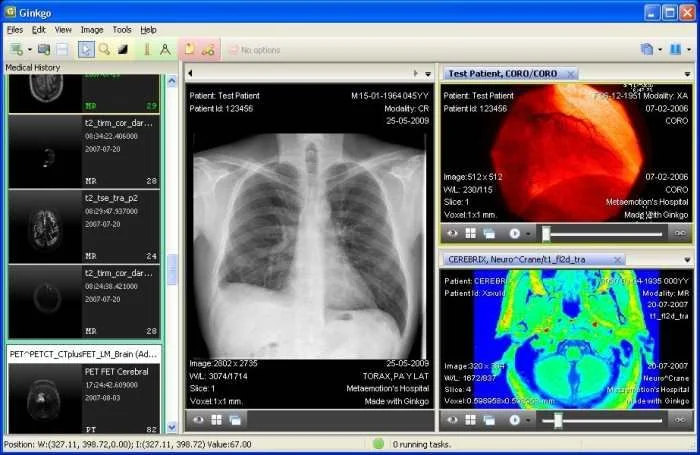

Популярные программы для просмотра DICOM-файлов (Windows, macOS, iOS, Android и Linux)

Видео-обзор лучших программ для просмотра DICOM-файлов